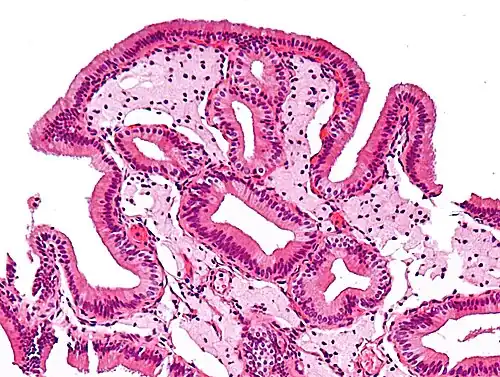

Micrograph of cholesterolosis of the gallbladder -

Micrograph of cholesterolosis of the gallbladder